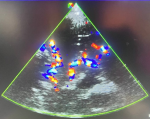

The transcranial Doppler examination procedure: the procedure was done with the patient in supine, with lateral tilting of his head to either side using the trans-temporal approach. Participants were scanned when well relaxed, but not asleep. The phase array probe was placed on the temporal aspect of the head, cephalad to the zygomatic arch and immediately anterior and slightly superior to the tragus of the ear in the transverse position. Then the probe was angulated anteriorly till the M1 segment of the middle cerebral artery was visualized on a color Doppler. Then, spectral wave analysis was done in the M1 segment on both sides. The trans-temporal view can examine the internal carotid artery bifurcation at the underlined depths with flow. The internal carotid artery was identified at depths of 55-65 mm with the simultaneous flow toward or away from the probe [18] on both sides of the participant´s head.

Figure 2: structure of the circle of Willis on color Doppler ultrasound